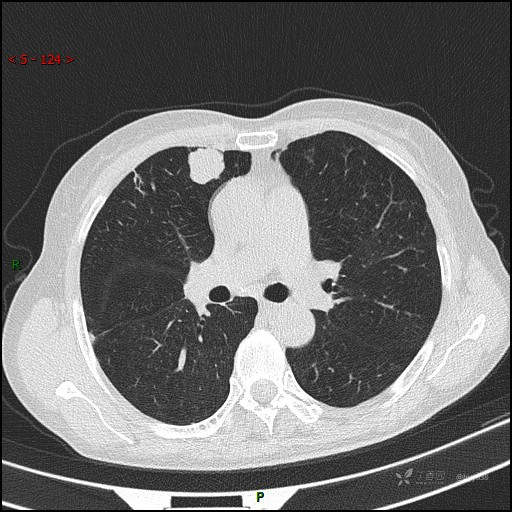

辅助检查:CT

讨论:病变性质?

静脉期

CT值